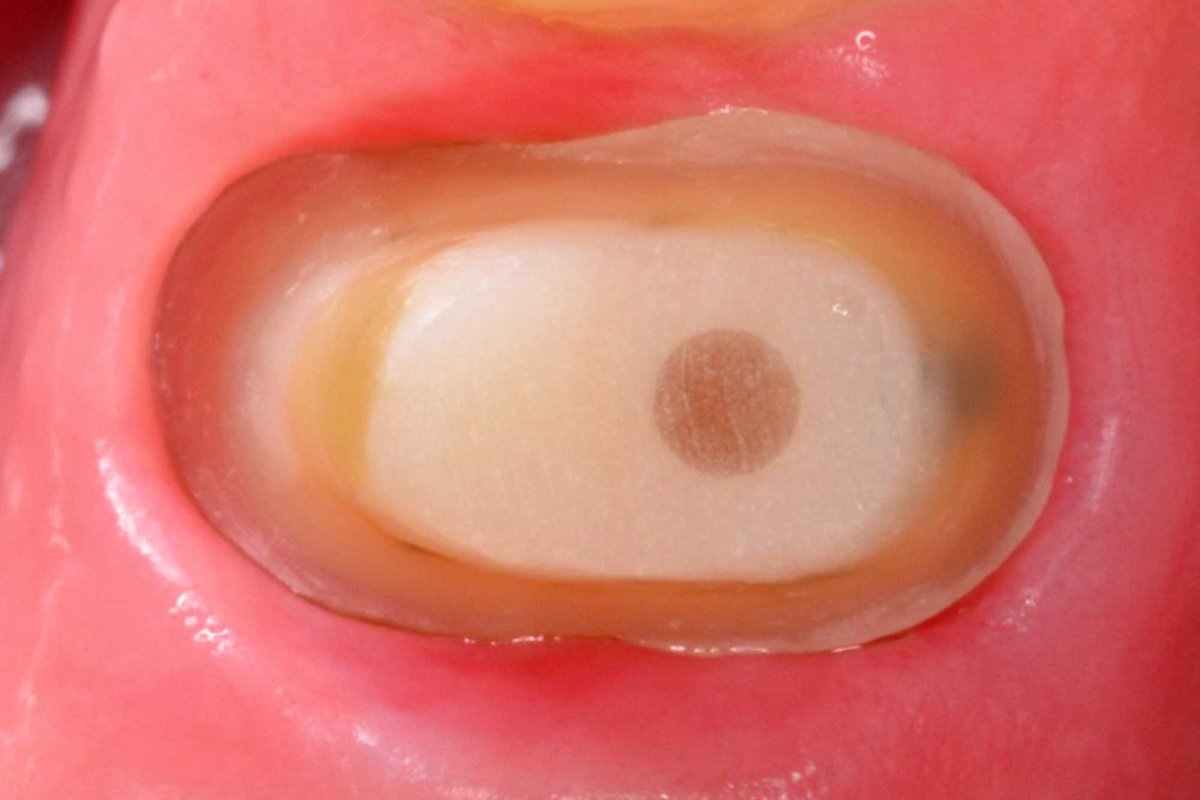

ماهي الطريقة المثالية لازالة القتابيركا لتثبيت الفايبربوست

كثير من الباحثين يفضلون ازالة القتابيركا بواسطة الحرارة gutta percha cutter device ولايفضلون الدريل rotary وذلك لتفادي حدوث أي ثقب في جدران القنوات. وبعد ازالتها بالحرارة ممكن استخدام الروتاري المناسب بقياس الفايبربوست

كيف نتجنب حدوث ثقوب في القنوات Perforation

دراسة على الاضراس الطاحنةKutller et al اظهرت التالي:

1) لاتستخدم Gates Glidden اكبر من مقاس 3. ليكن مقاس 3 هو الخيار الاخير

2) بعد علاج لب الاضراس غالبا ماتكون سماكة نقطة التقاء الجذور 1 ملم او أقل

3) طول الوتد اهم من سماكة الوتد